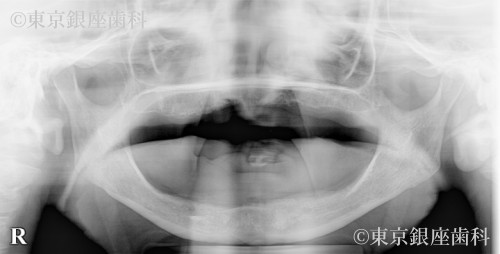

総入れ歯が合わず不便を感じていたが、上下ワンデイインプラントを選択。上顎には6本の埋入と骨補強を併用し、計画通りに進行。噛み合わせも改善し自然な見た目を取り戻した。

上下ワンデイインプラント(インプラント6本+骨補強)

腫れ・痛み・出血、骨が薄い場合の結合不全、再手術の可能性、噛み合わせ変化による違和感